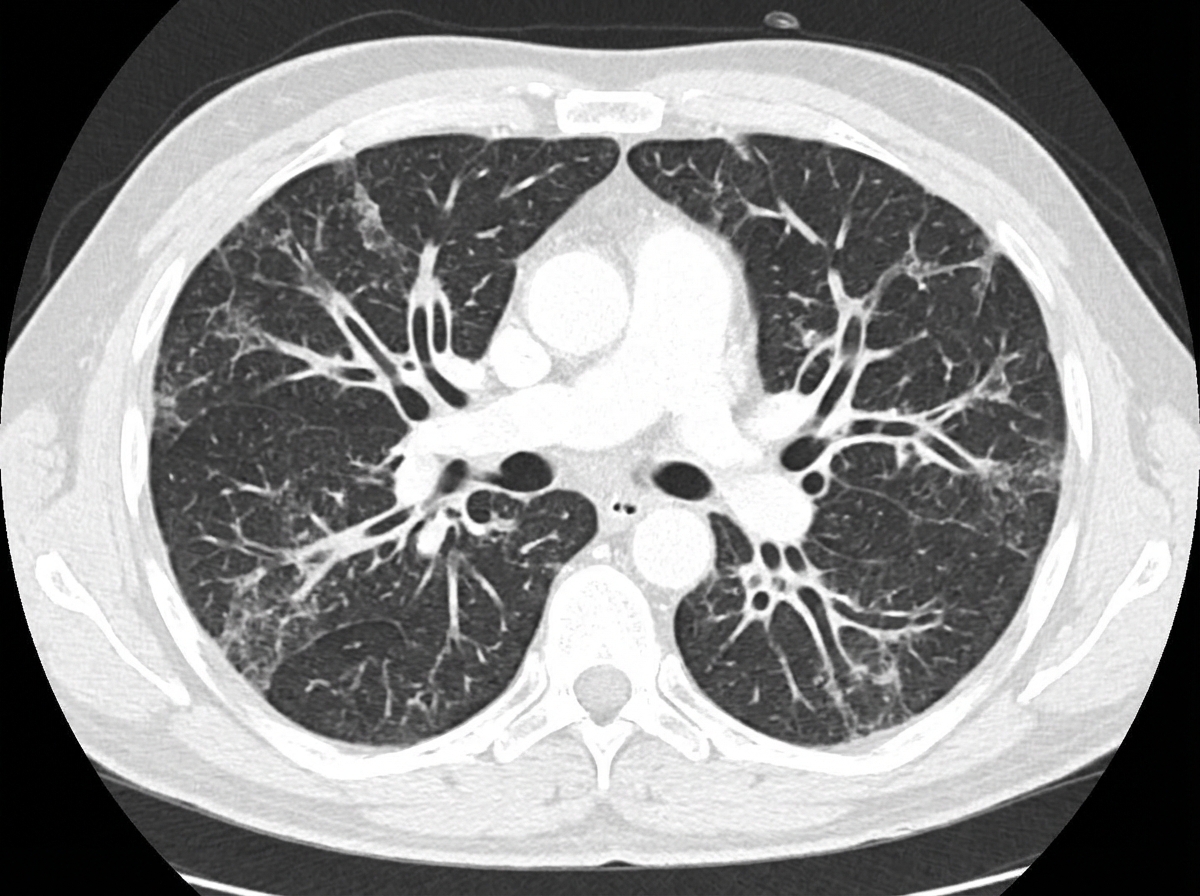

The CT chest of the patient shows the presence of which of the following?

Explanation: ***Bronchiectasis*** - CT chest shows characteristic **signet ring sign** (dilated bronchus with adjacent pulmonary artery) and **tram-track sign** (parallel bronchial walls). - Bronchi demonstrate **lack of normal tapering** and appear dilated with **thickened walls**, often in a cylindrical or varicose pattern. *Pneumatoceles* - Appear as **thin-walled air-filled cysts** within the lung parenchyma, typically following pneumonia or trauma. - Show **smooth, thin walls** without the bronchial pattern or wall thickening seen in bronchiectasis. *Normal scan* - Would show **normal bronchial tapering** with bronchi becoming progressively smaller toward the periphery. - Absence of **bronchial wall thickening**, cystic changes, or abnormal bronchial dilatation patterns. *Loculated empyema* - Presents as **loculated pleural fluid collections** with **enhancing pleural surfaces** on contrast-enhanced CT. - Shows **pleural thickening** and **septations** within the pleural space, not bronchial abnormalities.